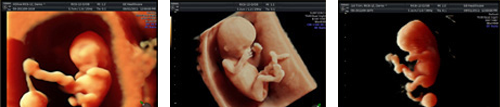

4D超音波は超音波映像を立体的に表現した3Dに、時間軸をプラスし、さらにリアルな動きを観察できるようにしたものです。

妊娠8週前後からお腹の赤ちゃんの様子を観察できるので、診察の場で活用しています。皆様により分かりやすい映像をご提供できるだけでなく、早期の胎児異常や、臍帯(さいたい)の位置などを知る手かがりにもなります。

当院では、HD Live機能を搭載した超音波を導入しています。HD Liveでは、胎児の立体像を内視鏡画像のようにリアルに表現することができ、特に妊娠初期の診断に効果を発揮します。

妊娠20週~29週に、4D超音波でお腹の中の赤ちゃんをご覧いただける外来です。